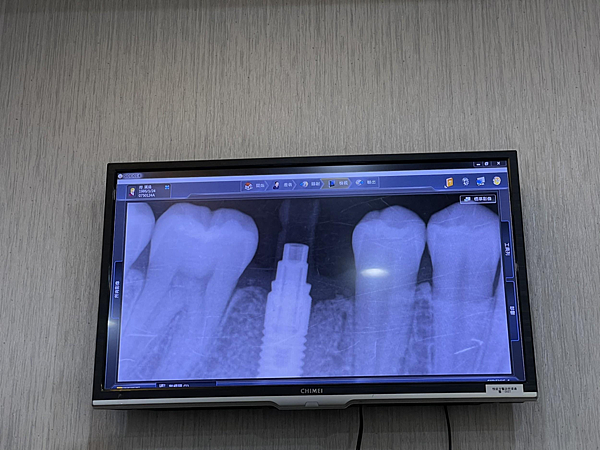

检查完缺牙的部分,就会被带去照全牙的x光,这样才能很仔细的看牙齿到缺陷跟如何能更仔细操作的植牙。

照完x光后李医生跟我解说我的牙根剩下的也非常的少,如果不做植牙的话 之后牙龈老化萎缩就会后面牙齿推挤前排,影响非常大~

这时候会再拍ㄧ次全牙的X光才能清楚知道骨头的生长程度